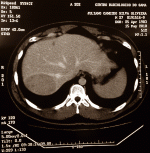

The doctors made a scan, which is shown below. The scan showed a suspicious patch measuring ten by eight by six centimetres in section VII of the liver, and it extended into sections VI and VIII.